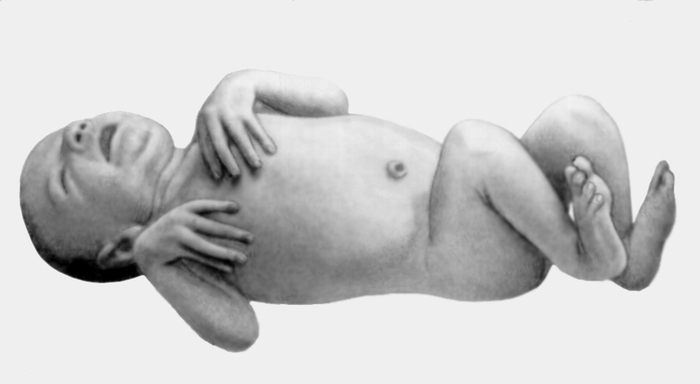

Neonatalnaya forma sindroma marfana klinicheskoe opisanie i kompleksnyj podhod k diagnostike i lecheniyu tema nauchnoj stati po klinicheskoj medicine chitajte besplatno tekst nauchno issledovatelskoj raboty v elektronnoj biblioteke kiberleninka (Тип файлу jpg)

Neonatalnaya Forma Sindroma Marfana Klinicheskoe Opisanie I Kompleksnyj Podhod K Diagnostike I Lecheniyu Tema Nauchnoj Stati Po Klinicheskoj Medicine Chitajte Besplatno Tekst Nauchno Issledovatelskoj Raboty V Elektronnoj Biblioteke Kiberleninka

Neonatalnaya forma sindroma marfana klinicheskoe opisanie i kompleksnyj podhod k diagnostike i lecheniyu tema nauchnoj stati po klinicheskoj medicine chitajte besplatno tekst nauchno issledovatelskoj raboty v elektronnoj biblioteke kiberleninka (Тип файлу jpg)

Neonatalnaya Forma Sindroma Marfana Klinicheskoe Opisanie I Kompleksnyj Podhod K Diagnostike I Lecheniyu Tema Nauchnoj Stati Po Klinicheskoj Medicine Chitajte Besplatno Tekst Nauchno Issledovatelskoj Raboty V Elektronnoj Biblioteke Kiberleninka